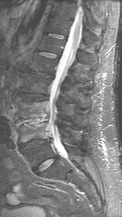

Спондилодисцит L3 – L4

4 процедуры ФДТ, 9 процедур MBST, 20 процедур ИПМТ

Параметры изменяются в зависимости от процедуры

Дата публикации: 22.08.2025 14:27:12

Грыжа Диска L4-L5

3 процедуры ФДТ, 9 процедур MBST